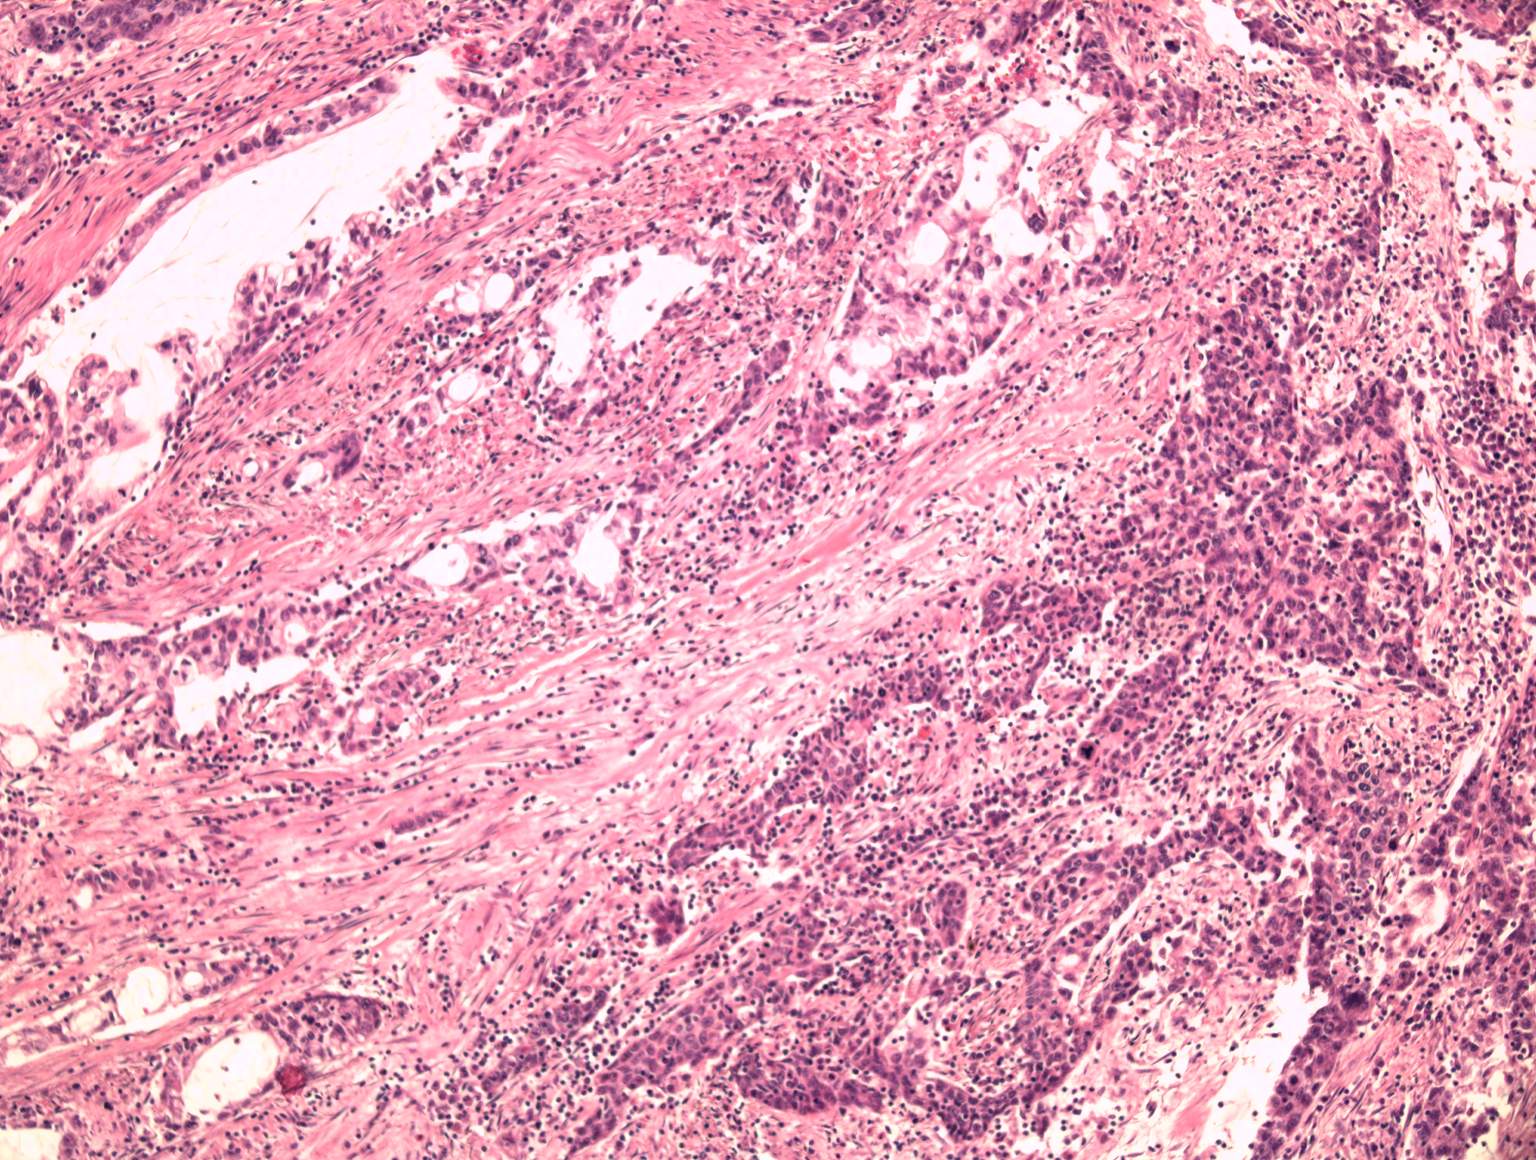

Undifferentiated carcinoma with ductal and

adenosquamous component

detail: x10